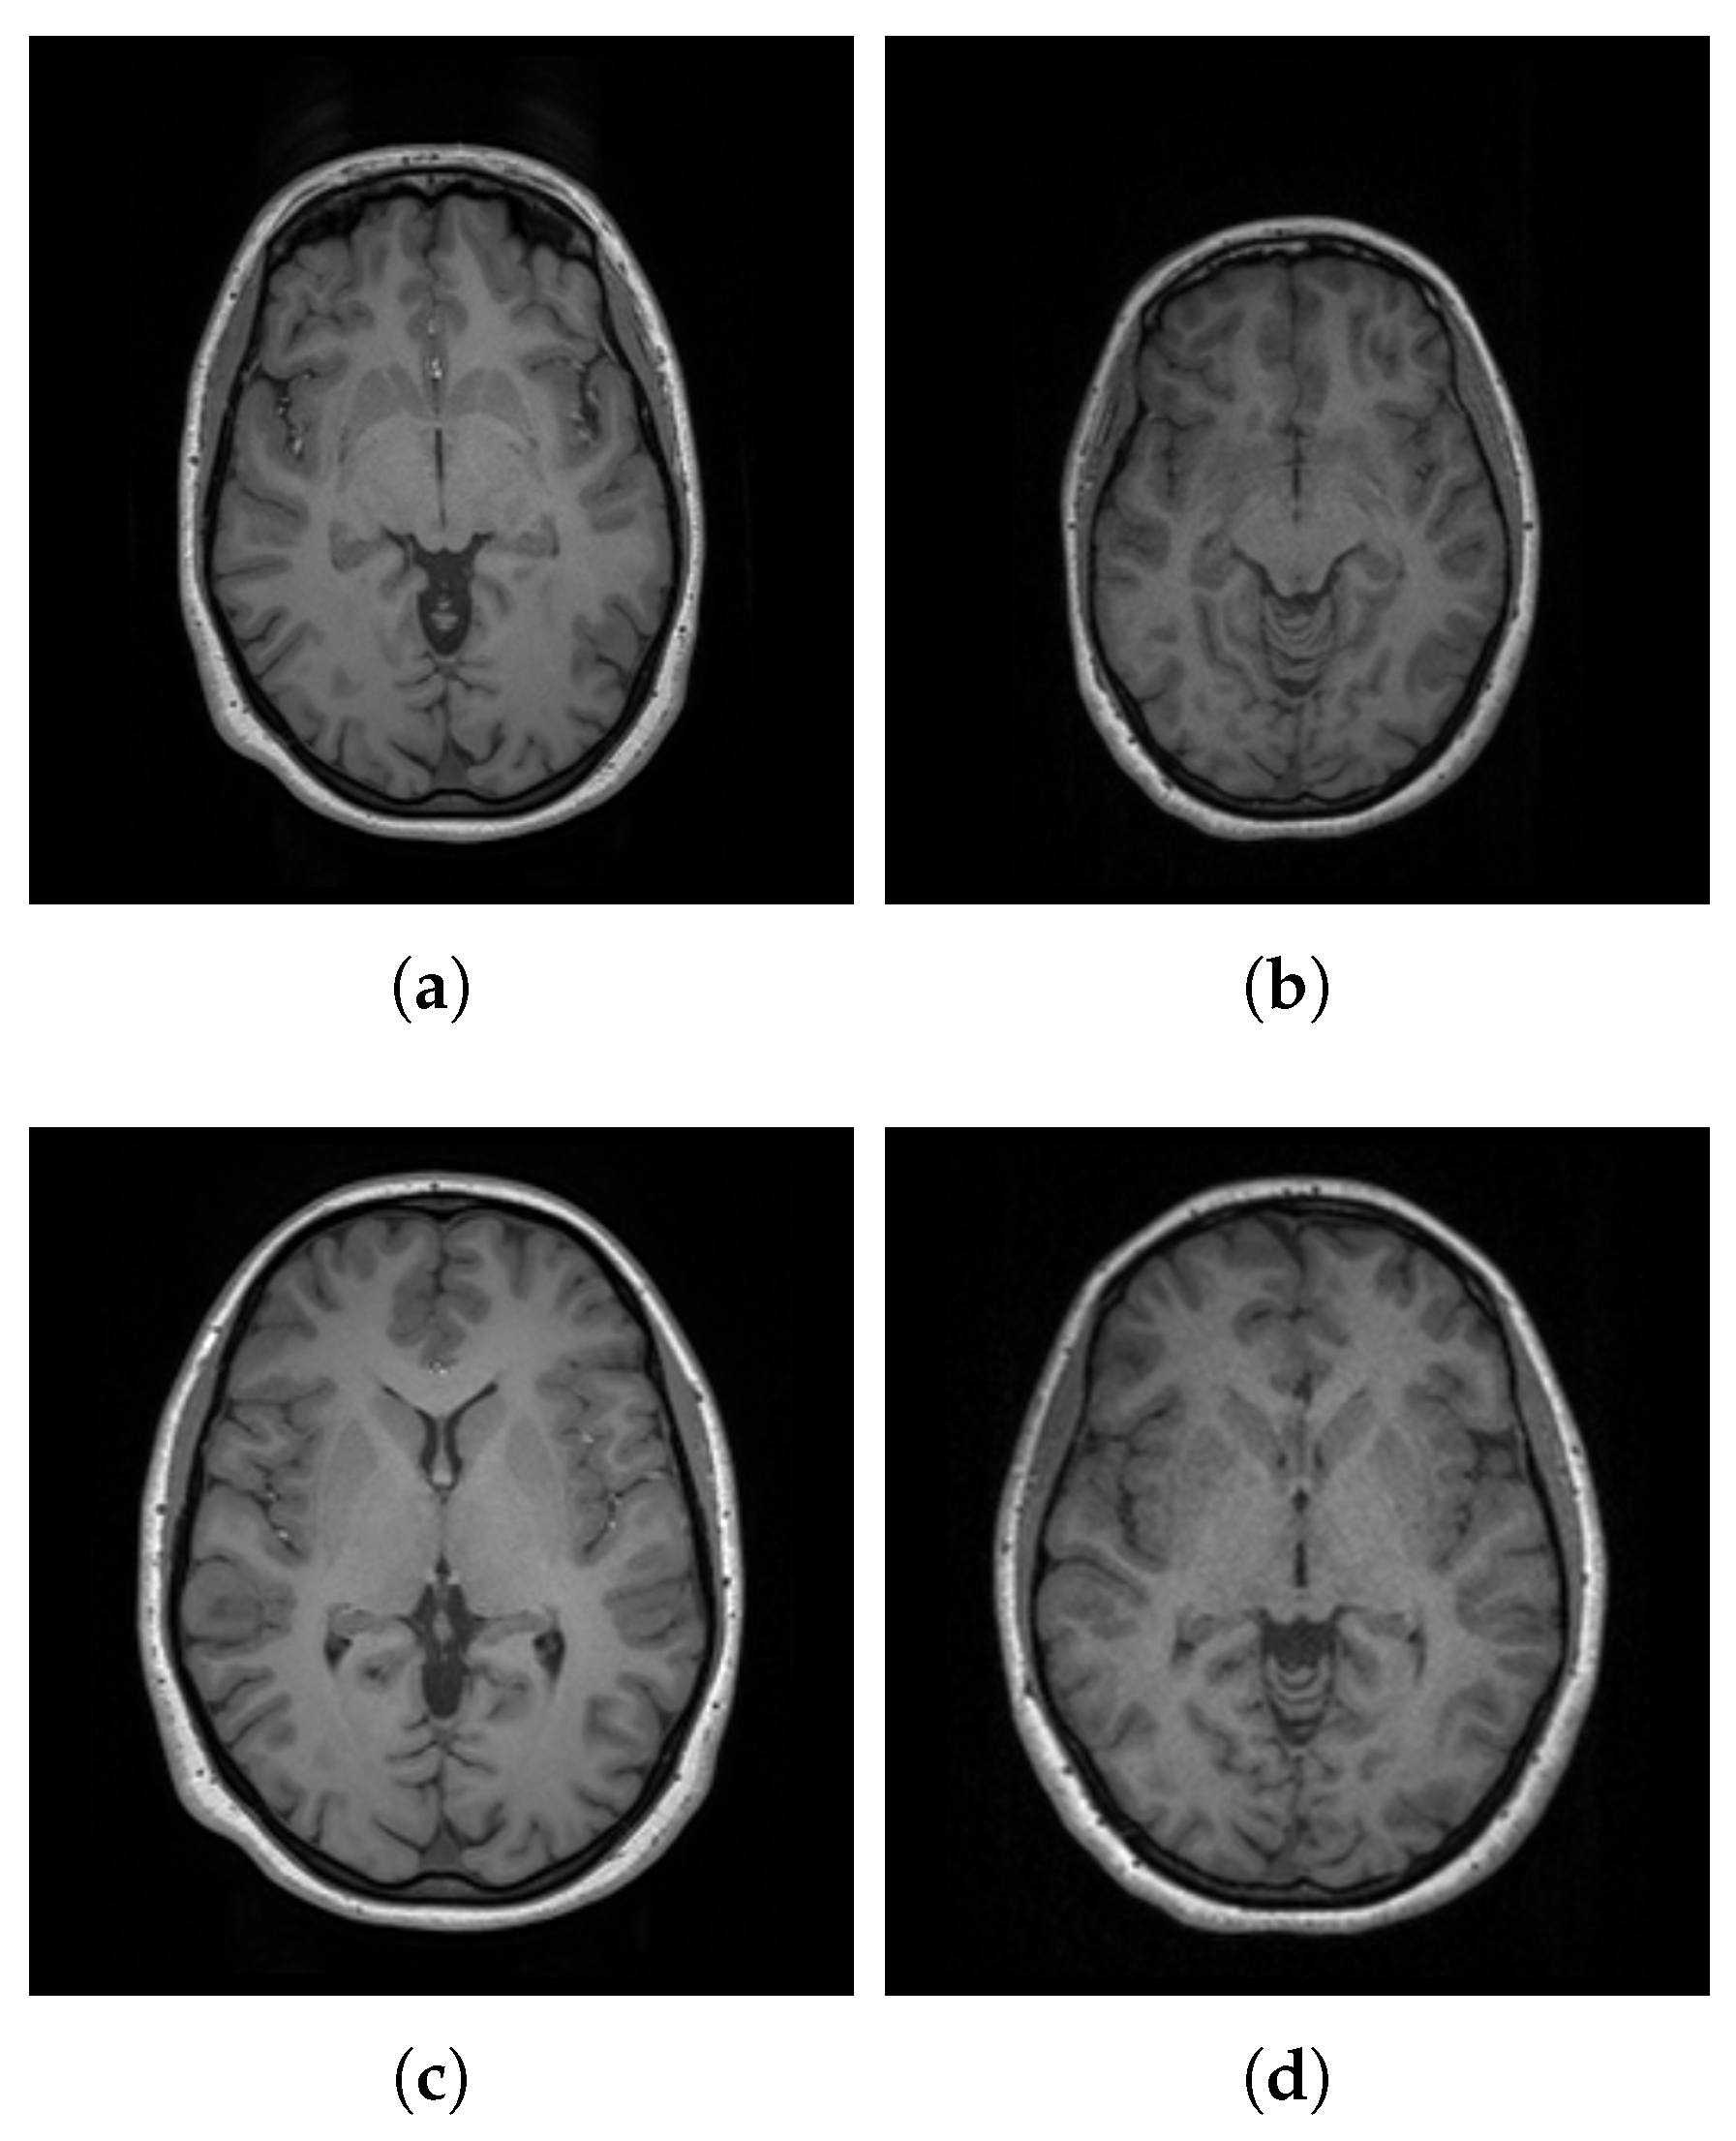

3.1. Dataset

3.2. Preprocessing